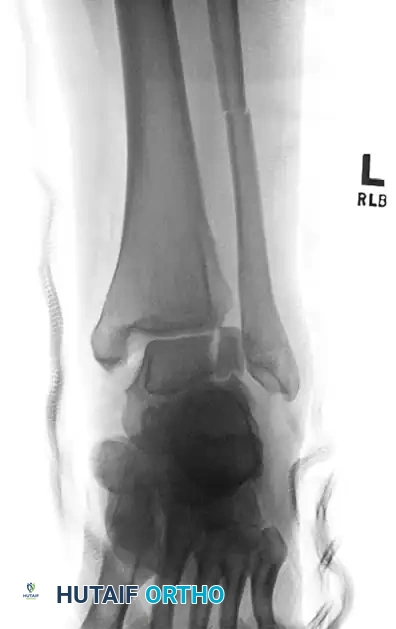

FIGURE 88-42 B: Attempted fixation of the talar body utilizing headless compression screws.

FIGURE 88-42 C: Concurrent fixation of the fibula with a neutralization plate and screws. Failure of such constructs often leads to the salvage pathways discussed herein.